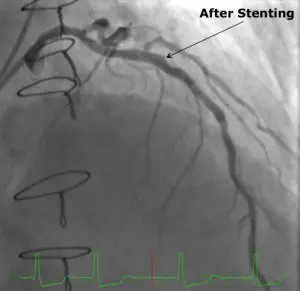

Dr. Ragosta performed a minimally invasive cardiac catheterization through the patient’s radial artery, placing a bare-metal stent into the LAD with excellent angiographic results. Because of the need for Plavix, surgery was delayed for at least four weeks.

Five weeks after the catheterization and stenting, Dr. Kern performed the aortic valve replacement. The patient was placed on cardiopulmonary bypass via the right axillary artery and femoral vein in order to minimize risk of cardiac injury, and the previous sternotomy incision was reopened. Minimal dissection of the heart and previous bypass grafts was required because the LAD had already been revascularized. The operation lasted approximately four hours and there were no complications.